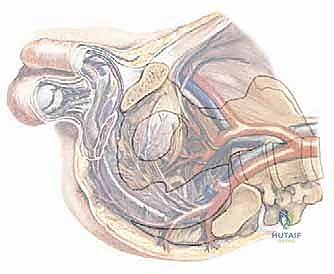

لفهم مدى تعقيد عملية بتر النصف الحوضي، يجب أولاً فهم تشريح الحوض. الحوض ليس مجرد عظمة واحدة، بل هو حلقة عظمية قوية تدعم العمود الفقري وتربطه بالأطراف السفلية. يتكون كل نصف من الحوض (العظم اللامسمى) من ثلاثة أجزاء مندمجة: الحرقفة (Ilium)، الإسك (Ischium)، والعانة (Pubis).

التحدي الأكبر في هذه الجراحة لا يكمن فقط في العظام، بل في الشبكة الكثيفة من الأوعية الدموية الحيوية (مثل الشريان والوريد الحرقفي) والأعصاب الرئيسية (مثل العصب الوركي) التي تمر عبر هذه المنطقة. أي خطأ طفيف قد يؤدي إلى نزيف كارثي أو تلف عصبي دائم.

في تقنية السديلة الخلفية (Posterior Flap)، يتم التركيز على الحفاظ على العضلة الألوية الكبرى (Gluteus Maximus) والجلد المغطي لها من الجهة الخلفية. هذه السديلة (الرفرفة العضلية الجلدية) تعتبر حاسمة جداً، لأنها ستُستخدم لتغطية الجرح الكبير الناتج عن البتر، وتوفر وسادة نسيجية قوية تسمح للمريض بالجلوس بشكل مريح لاحقاً واستخدام الأطراف الصناعية.